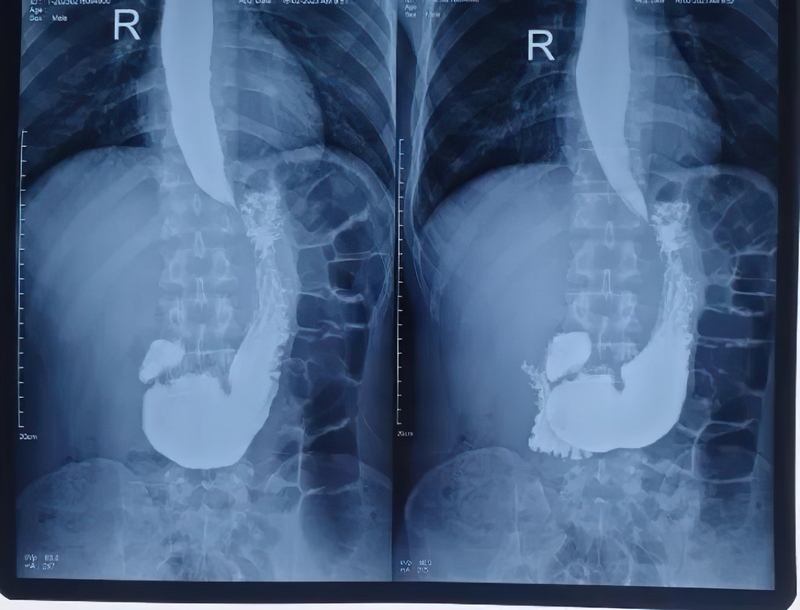

Chụp X quang dạ dày là một kỹ thuật chẩn đoán hình ảnh quan trọng và được áp dụng phổ biến để phát hiện, theo dõi các bệnh lý liên quan đến dạ dày. Để thực hiện kỹ thuật này cần có máy chụp X quang có thể phát ra các tia X - các tia bức xạ năng lượng cao. Tia X được phát ra máy chụp có thể đi xuyên qua cơ thể của chúng ta. Khi nó đi xuyên qua vùng bụng chứa dạ dày, tia X sẽ tiếp tục đi đến phim X quang có vai trò là tấm thu nhận hình ảnh Lúc này, hình ảnh dạ dày và các cấu trúc khác bên trong khoang bụng của người bệnh sẽ được hiển thị trên phim chụp X quang.

Khác với chụp X quang thông thường, chụp X quang dạ dày cần dùng thuốc cản quang. Thuốc cản quang (barium) là một loại muối kim loại, không bị nước hay các dung môi hữu cơ hòa tan nên khá an toàn với sức khỏe. Khi người bệnh dùng thuốc cản quang, những tổn thương tại thực quản, dạ dày, tá tràng của người bệnh sẽ được hiển thị rõ hơn trên phim chụp. Điều này giúp các bác sĩ có thể quan sát dễ dàng và đưa ra những chẩn đoán bệnh chính xác hơn. Chụp X quang có ảnh hưởng gì không? Về cơ bản, đây là kỹ thuật chẩn đoán hình ảnh an toàn, ít tác dụng phụ và không xâm lấn.